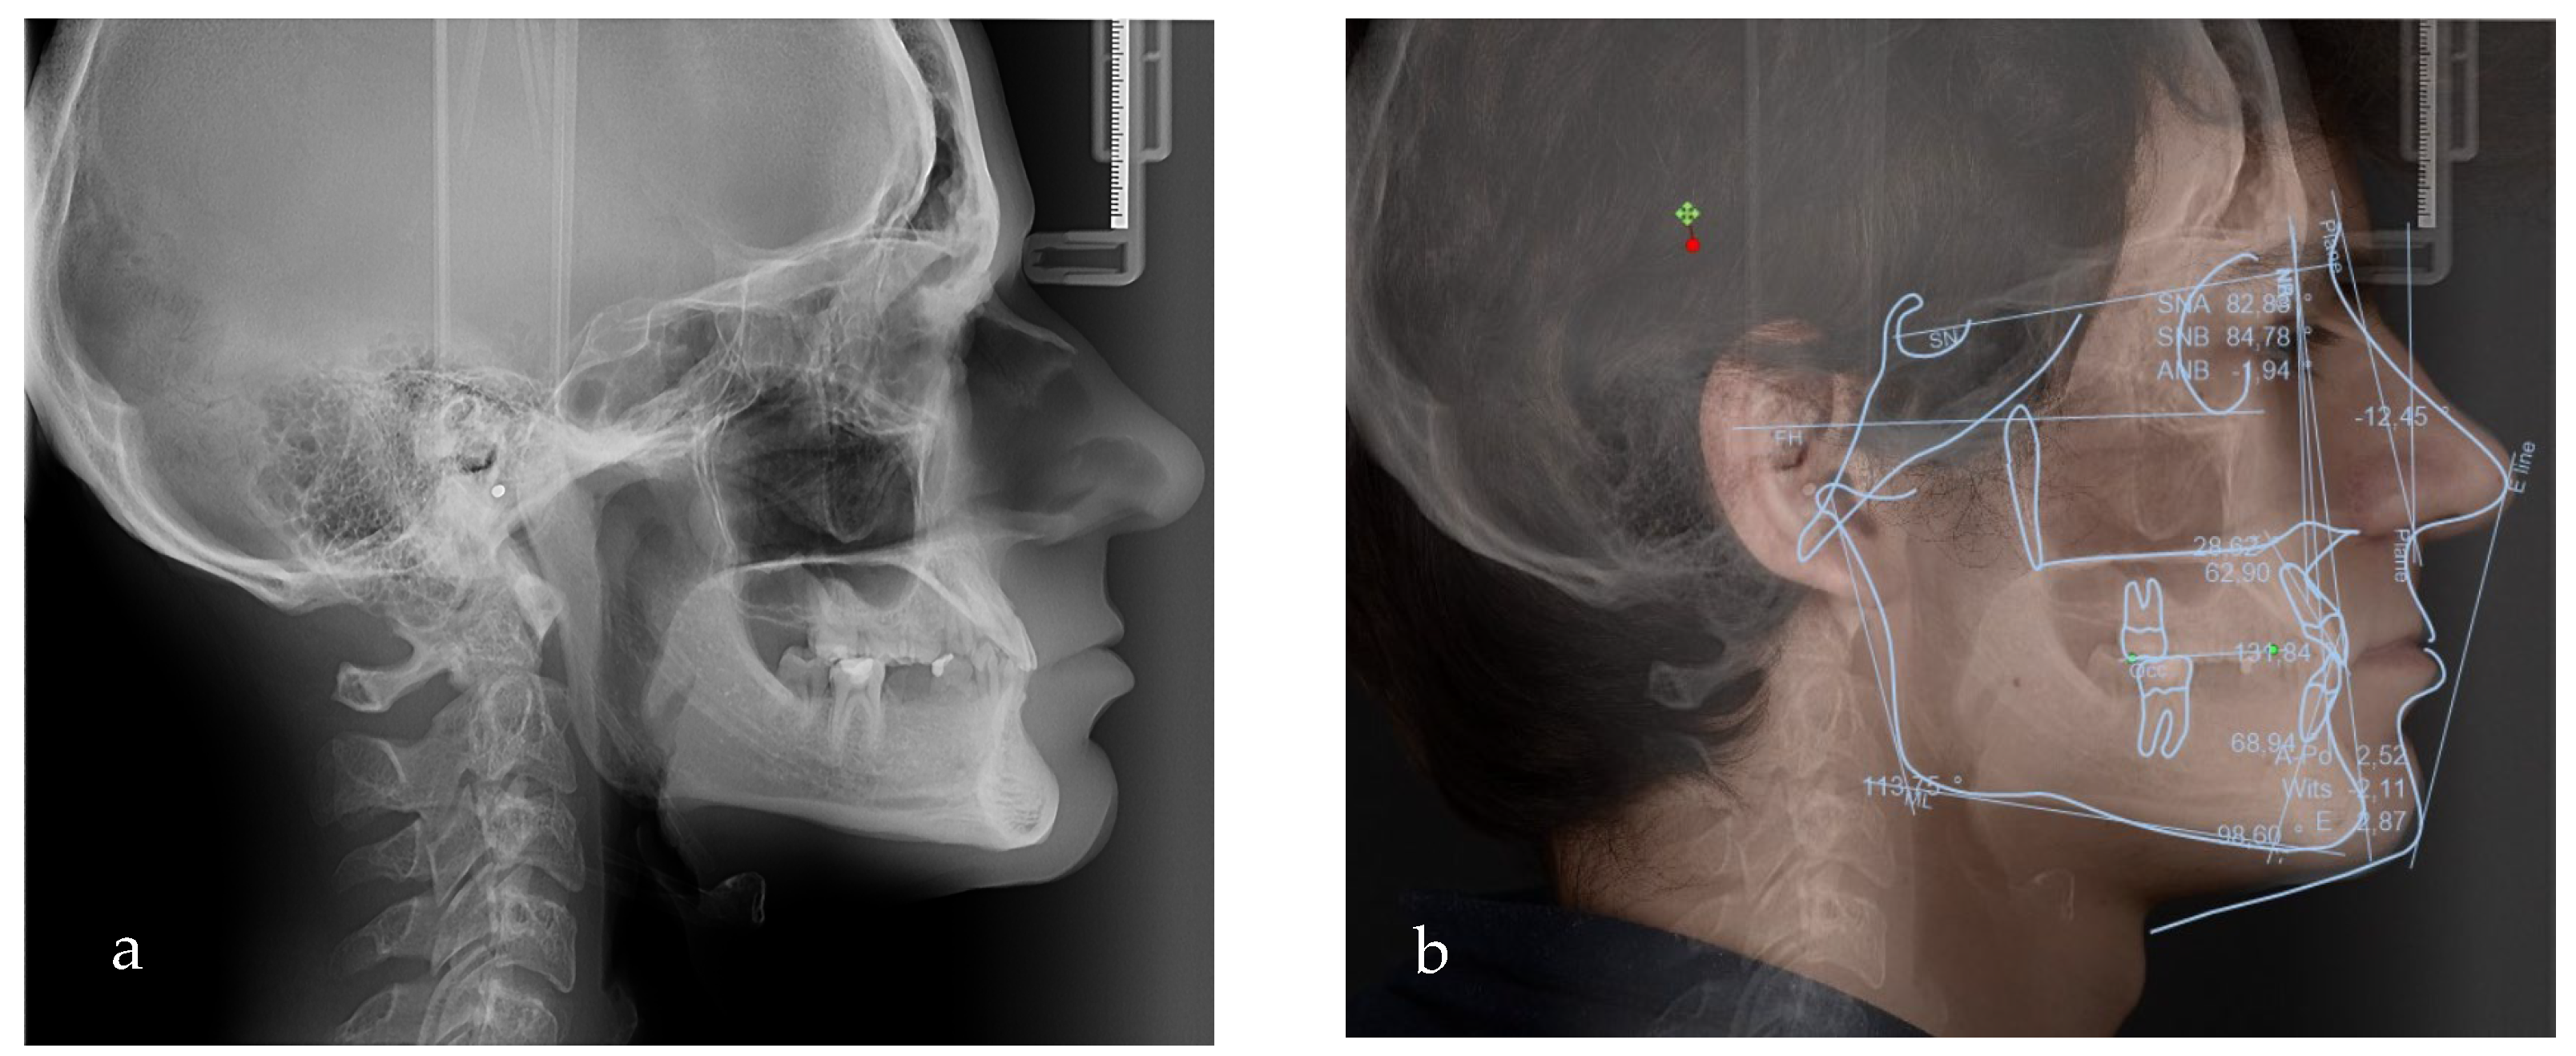

Figure 5.

(a) Lateral teleradiograph; (b) VTO analysis.

Based on the clinical and paraclinical examination, the following diagnostics were established: skeletal and dental class III anomaly (ANB angle −1°), with hypodivergent growth pattern and anterior rotation of the mandible (Sn-GoGn 28°), maxillary hypoplasia, slightly protruded upper incisors, diastema, spacing due to anodontia of the lower central incisors, all lateral incisors, all canines, all premolars and three second molars. Therefore, in this clinical case, seven permanent teeth were present.

To evaluate the treatment options and the amount of posterior rotation of the jaws required to improve the facial appearance, the VTO (Romexis) was formed (Figure 5b).

Based on the VTO (visualized treatment objective), protraction and posterior rotation of the maxilla would have been the ideal treatment option in terms of skeletal modifications; however, this treatment option would have needed an orthognathic surgical approach (which was not accepted by the patient).